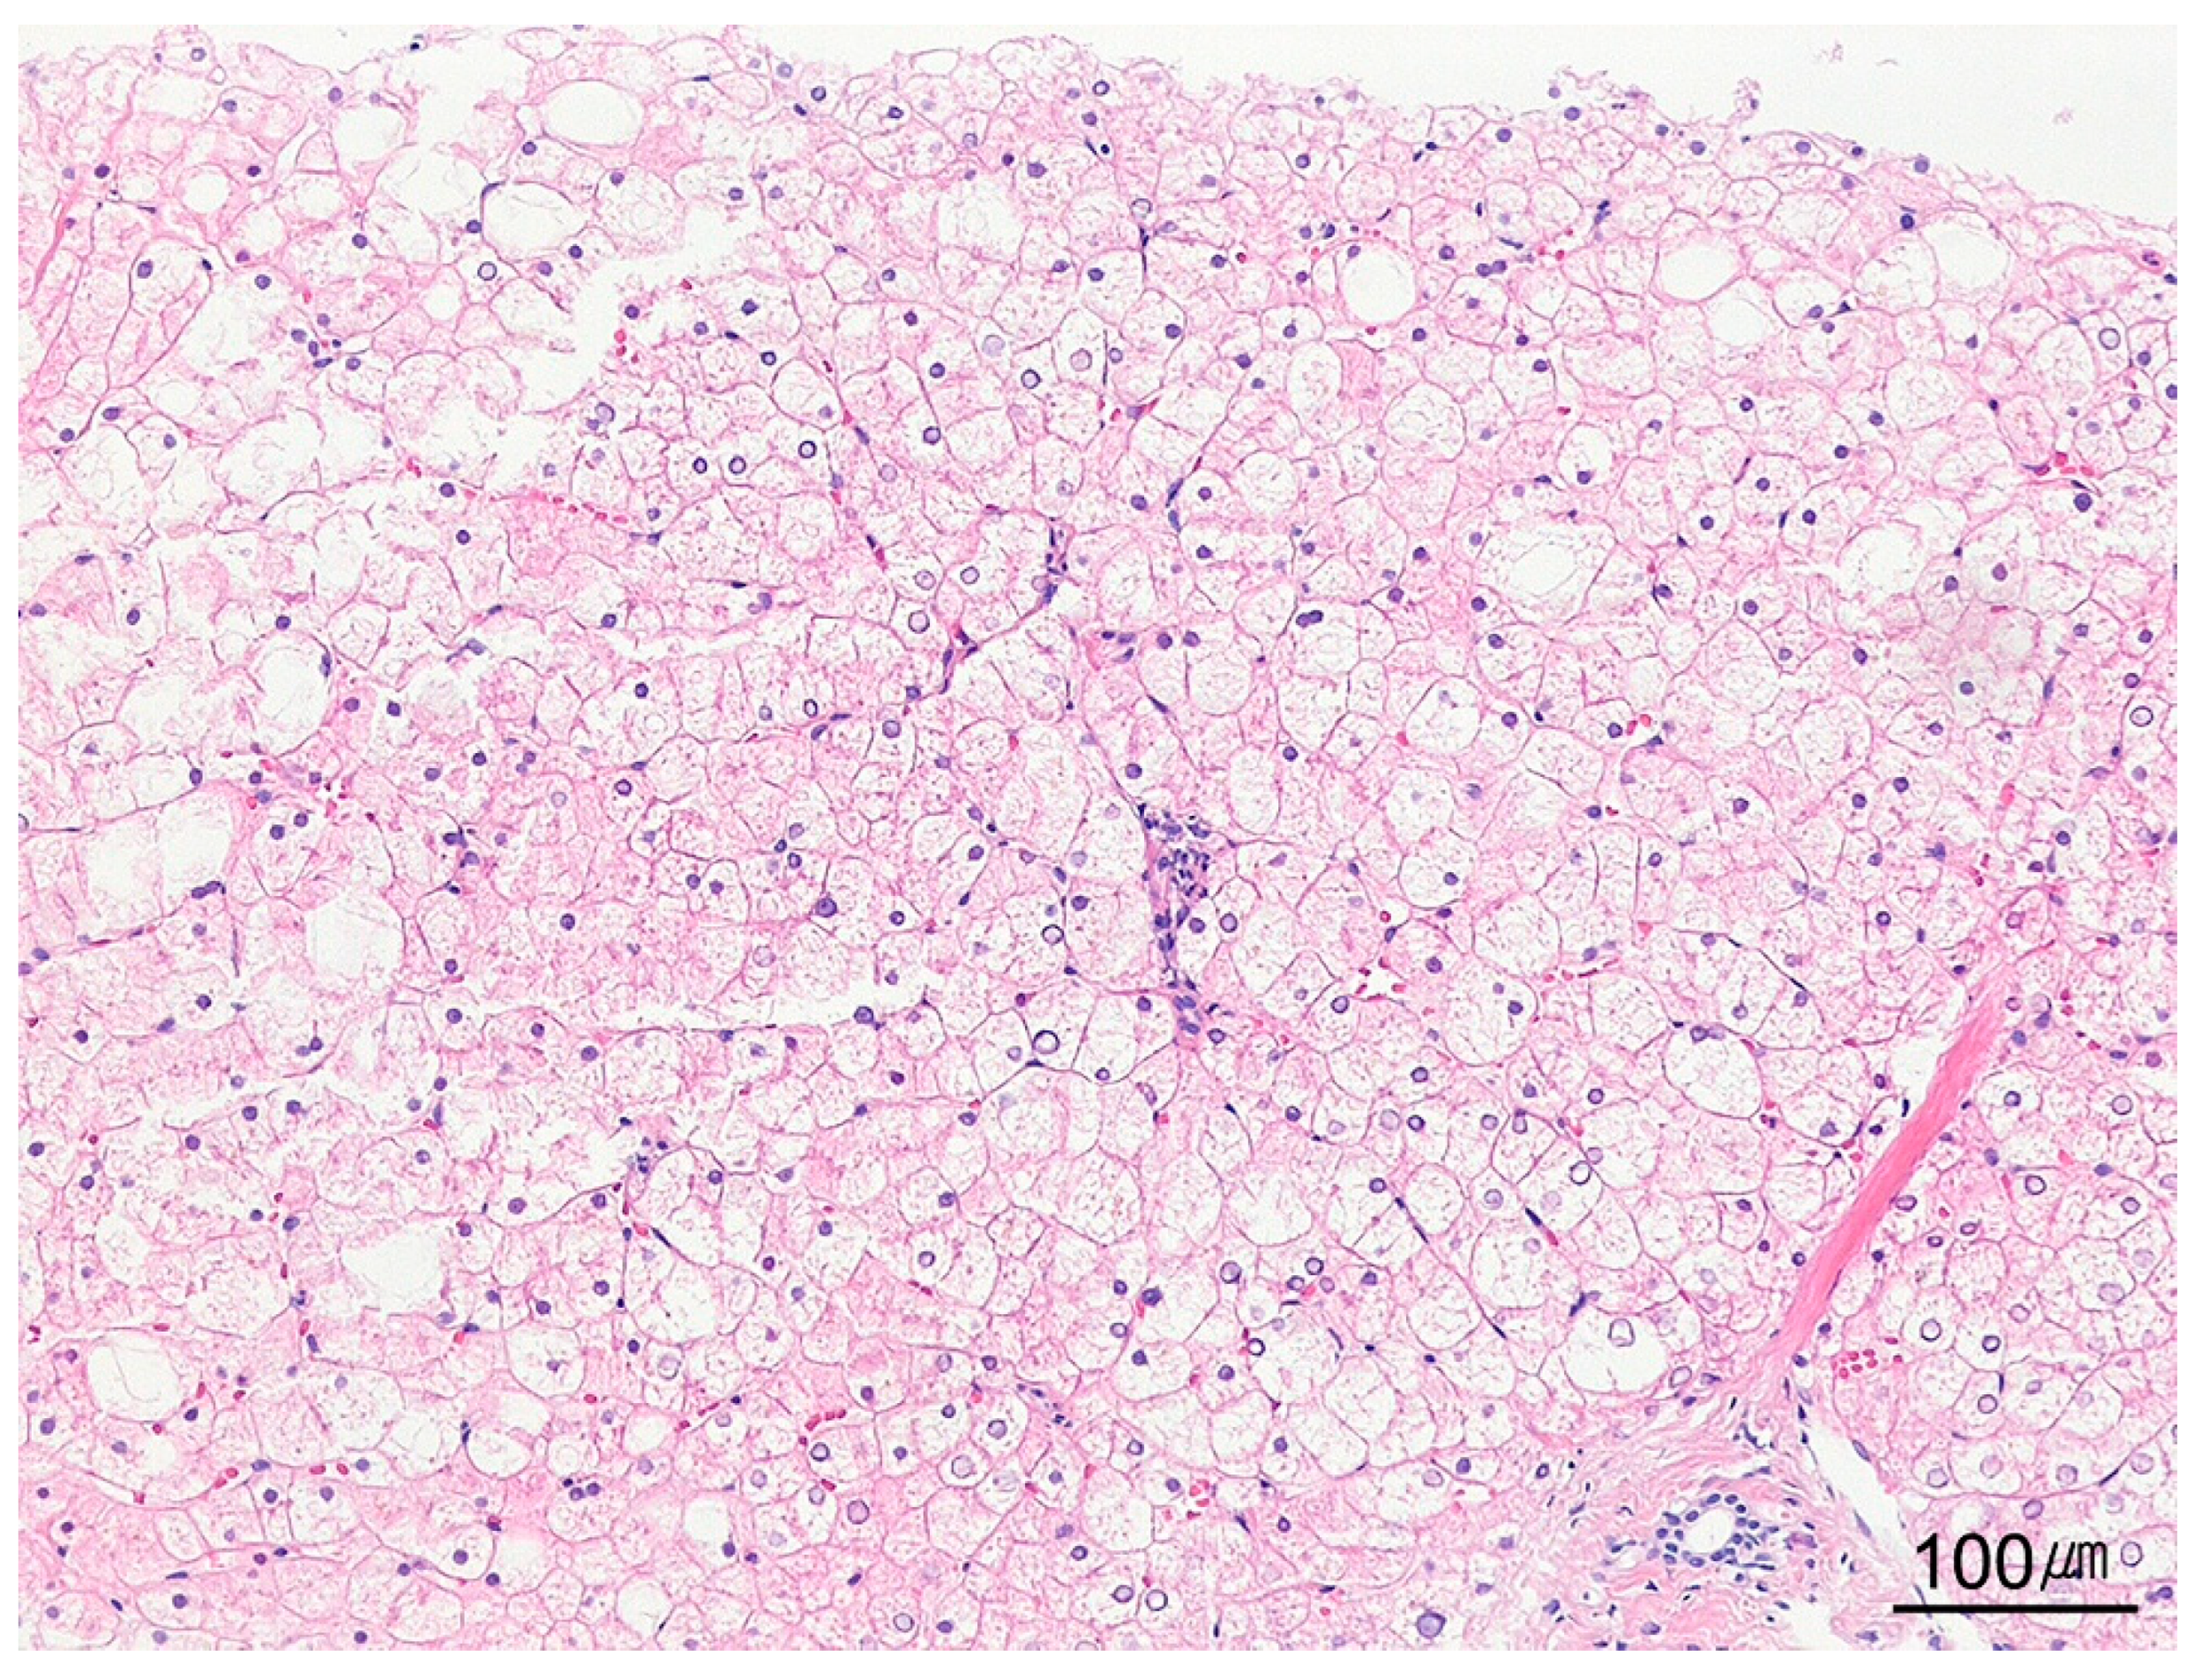

9.4. Cytoplasmic Changes and Inclusions in Hepatocytes

| Steatotic pattern | Macrovesicular steatosis Microvesicular steatosis | Alcohol-associated liver disease NAFLD/NASH (metabolic syndrome) DILI |